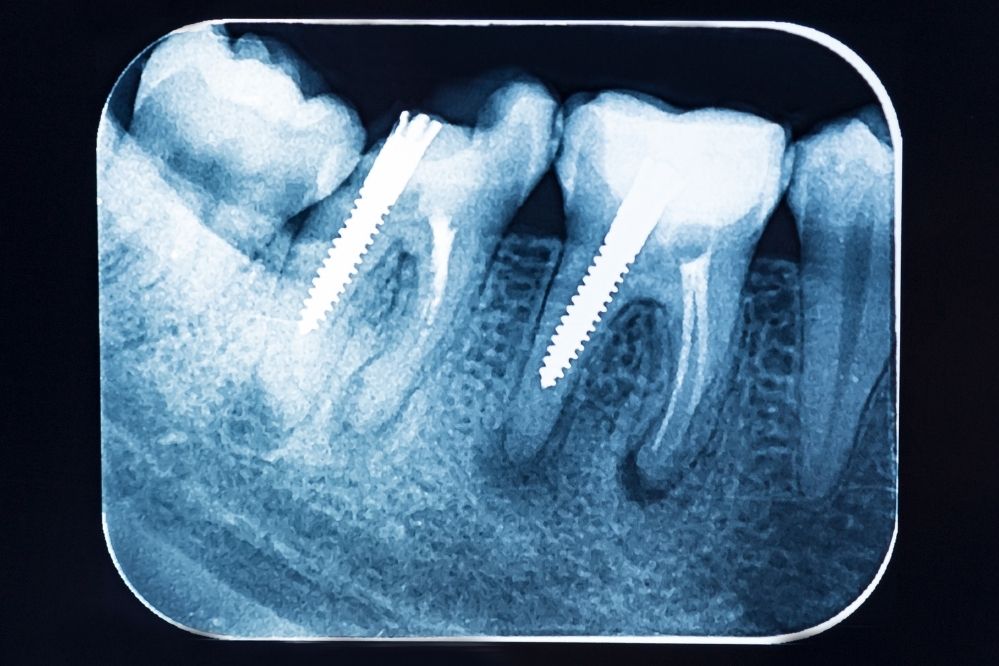

El tratamiento dependerá del estado del diente al momento de la revisión. Generalmente, las opciones son:

- Recolocación o reemplazo del empaste si el diente está sano

- Limpieza profunda de la cavidad y nuevo empaste

- En casos más avanzados: reconstrucción con incrustaciones o coronas

- Si hay daño en el nervio: endodoncia